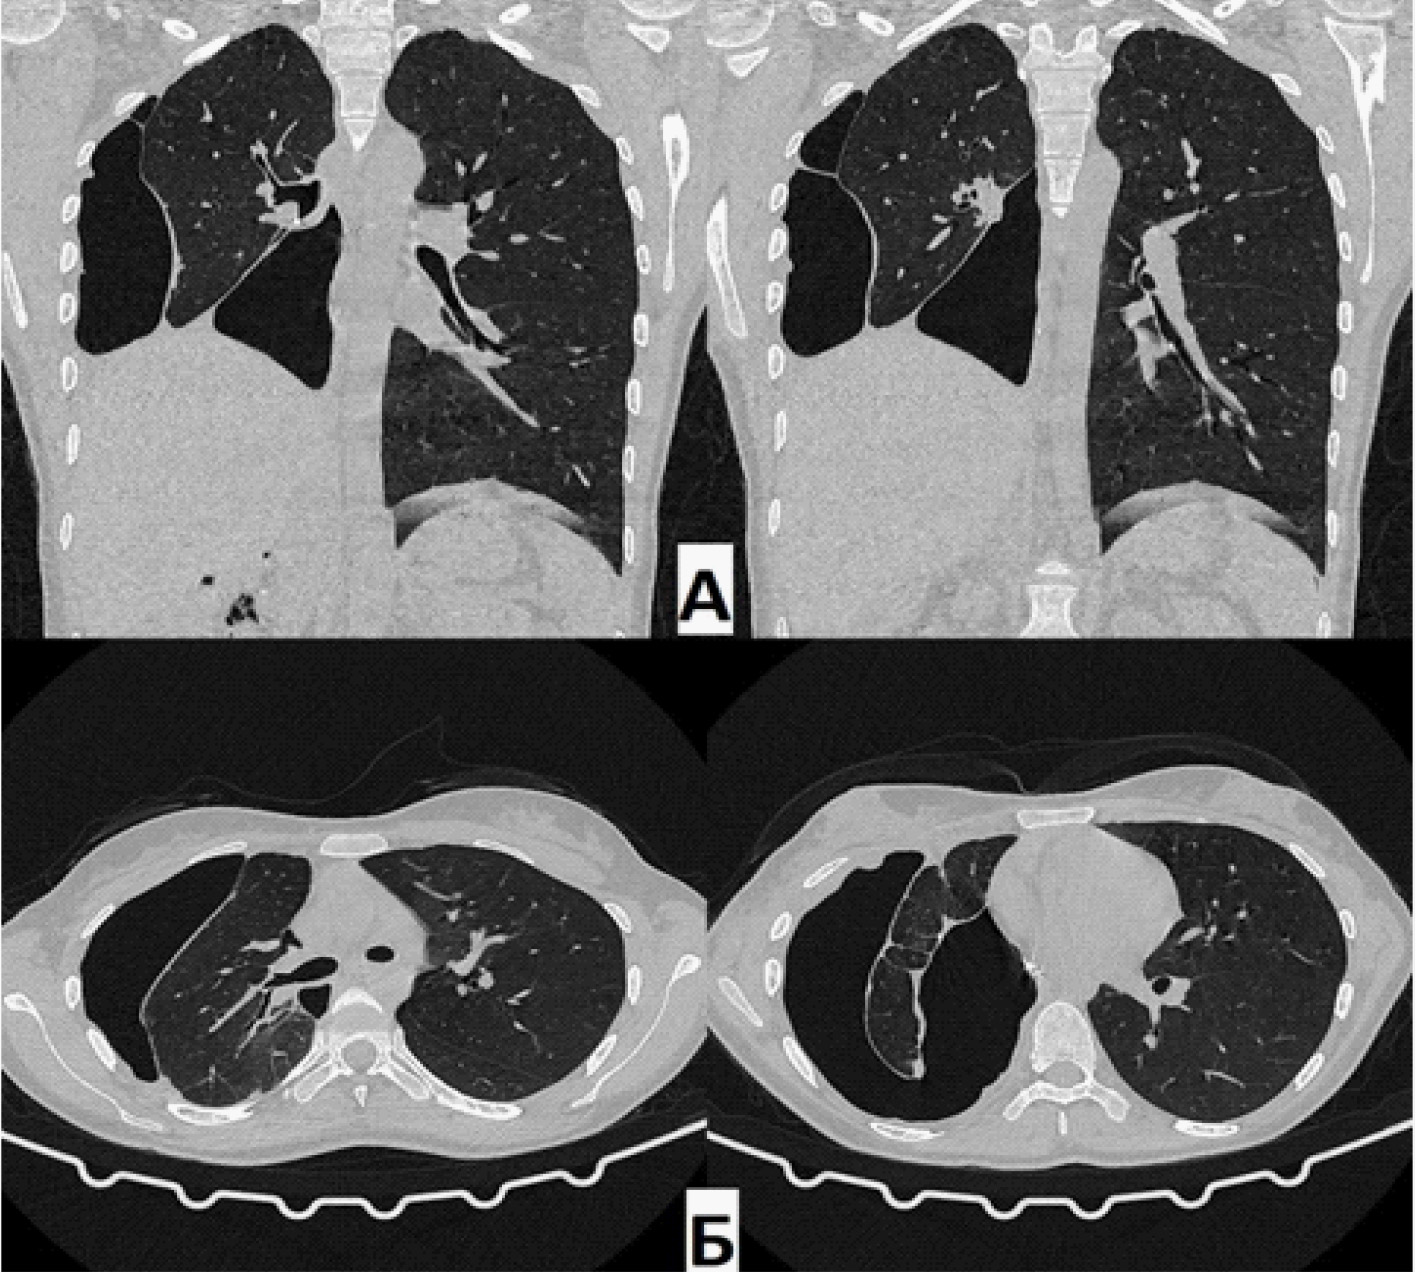

На КТ органов грудной клетки (от 21 июня 2021 г.) определялось бронхоплевральное сообщение культи правого промежуточного бронха с плевральной полостью. Остаточная плевральная полость (ОПП) в нижних отделах справа. В оставшихся отделах правого легкого – без патологических изменений (очаговых и инфильтративных теней не обнаружено). Тень средостения располагается срединно, правый купол диафрагмы приподнят до уровня VI межреберья (рис. 1).

Рис. 1. Компьютерная томография (А – фронтальная проекция; Б – аксиальная проекция) при поступлении. Определяется остаточная полость парамедиастинально слева